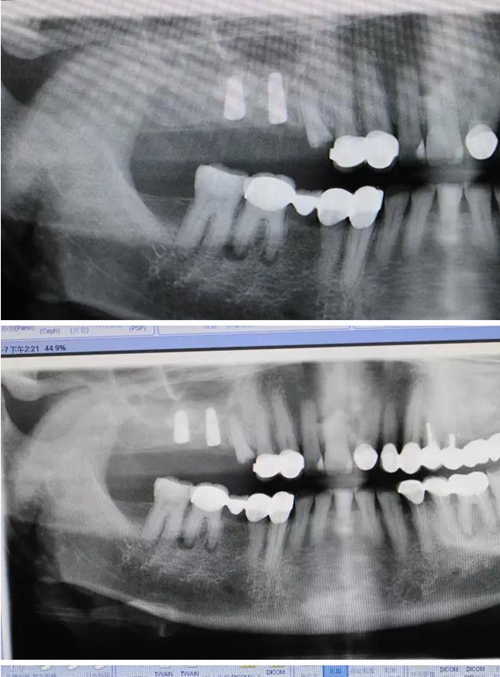

【病例分享】右上內(nèi)提+5冠延長1 梁光強